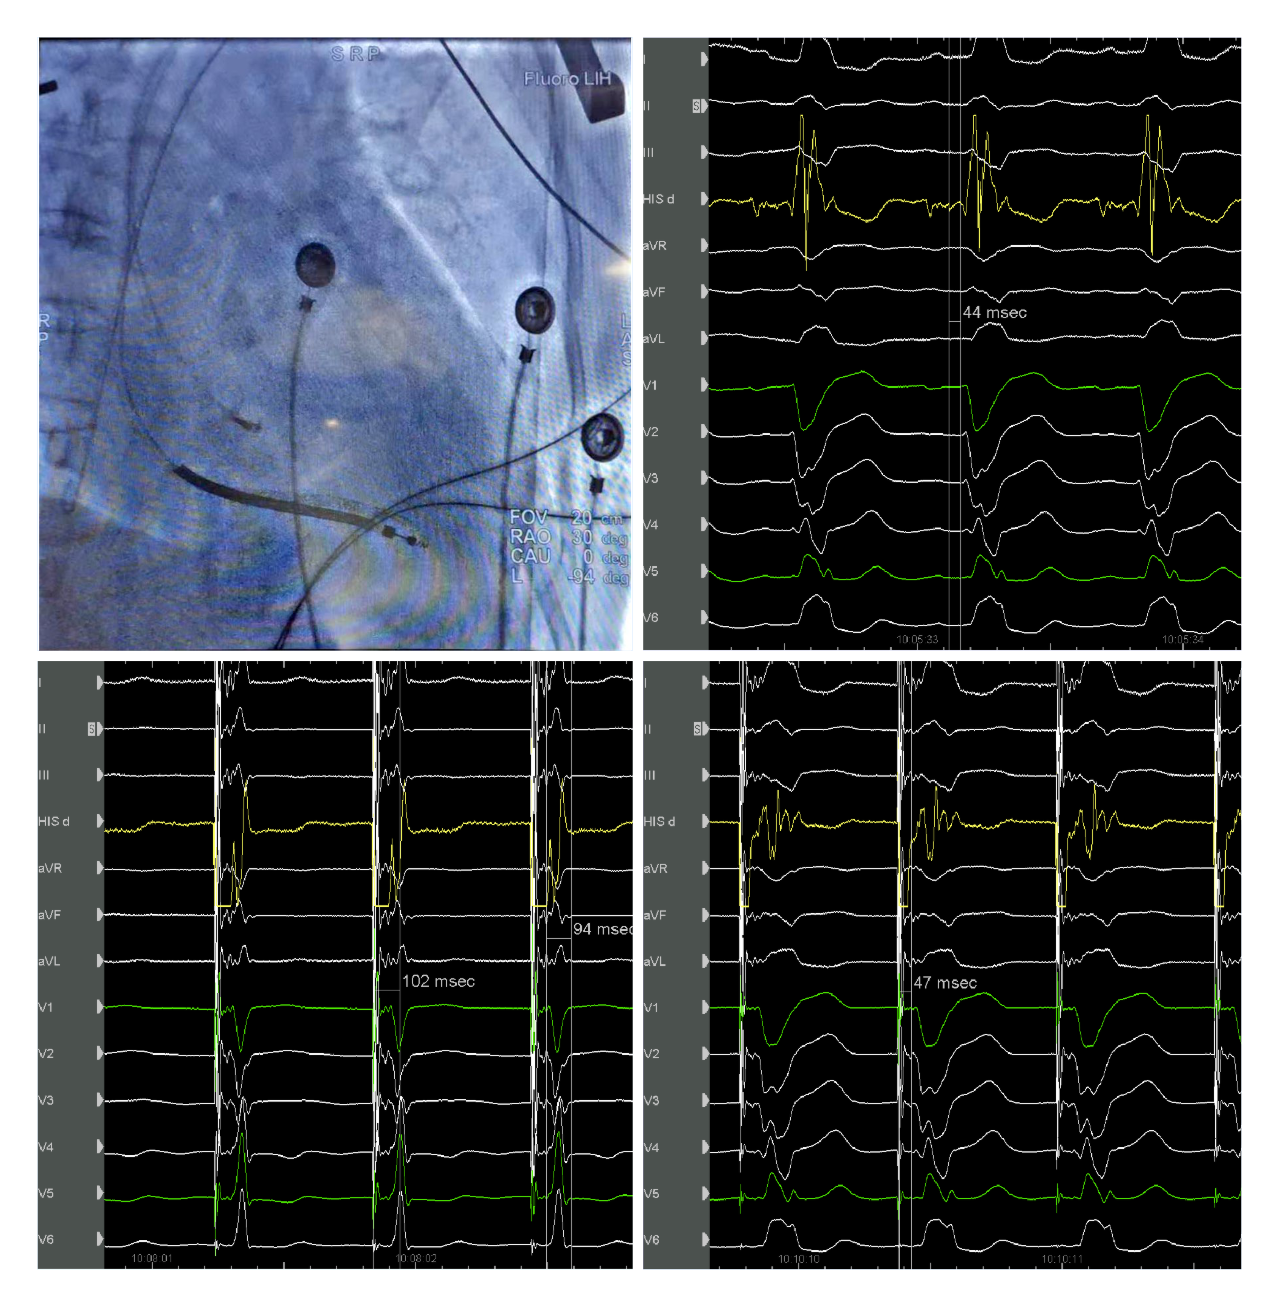

爱情岛论坛 起搏团队演示了一例左束支起搏纠正完全性左束支阻滞用于治疗经典CRT适应症的病例。该患者为女性, 69岁,诊断:扩张型心肌病,完全性左束支传导阻滞,心功能III级,心电图显示经典完全性左束支阻滞图形,QRS193ms,心超LVD 73mm,EF 30%,符合CRTD适应症。术中顺利穿刺左侧腋静脉,在C315鞘管导引下3830电极标记到HIS电位,高电压起搏可纠正左束支阻滞,但纠正阈值较高8V/1.5ms。

(上图左上为希氏束的影像位置;右上为希氏束电位图;右下为低电压选择性希氏束起搏波型与自身一致;左下为高电压8V/1.5ms希氏束起搏纠正完左)

随后3830导线往心尖方向前移1cm拧入,同时监测起搏图形及单极阻抗,到位后起搏心电图显示不完全性右束支阻滞图形,左束支阻滞消失,测量V5导联左室达峰时间84ms,单双极高低电压起搏一致,提示夺获了左束支,夺获阈值0.7V/0.5ms。

(上图中左上为单极高电压起搏,右上为单极低电压起搏,左下为双极高电压起搏,右下为双极低电压起搏)